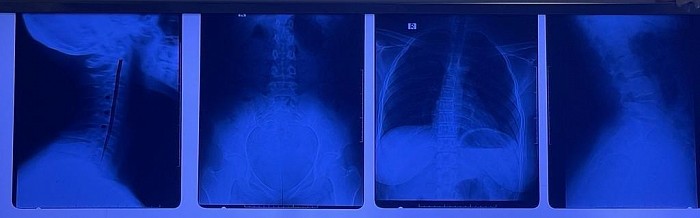

La chirocoppettazione è il corretto allineamento delle vertebre, la sessione non termina finché il paziente non si sente bene.

Il dottor Christian Pickmans. 19 anni di esperienza laureato presso l'Università Saõ Carlos - Brasile. Studi effettuati: chiropratica brasiliana, medicina ayurvedica, dissezione umana, medicina cinese e medicina araba Hiyama dan.